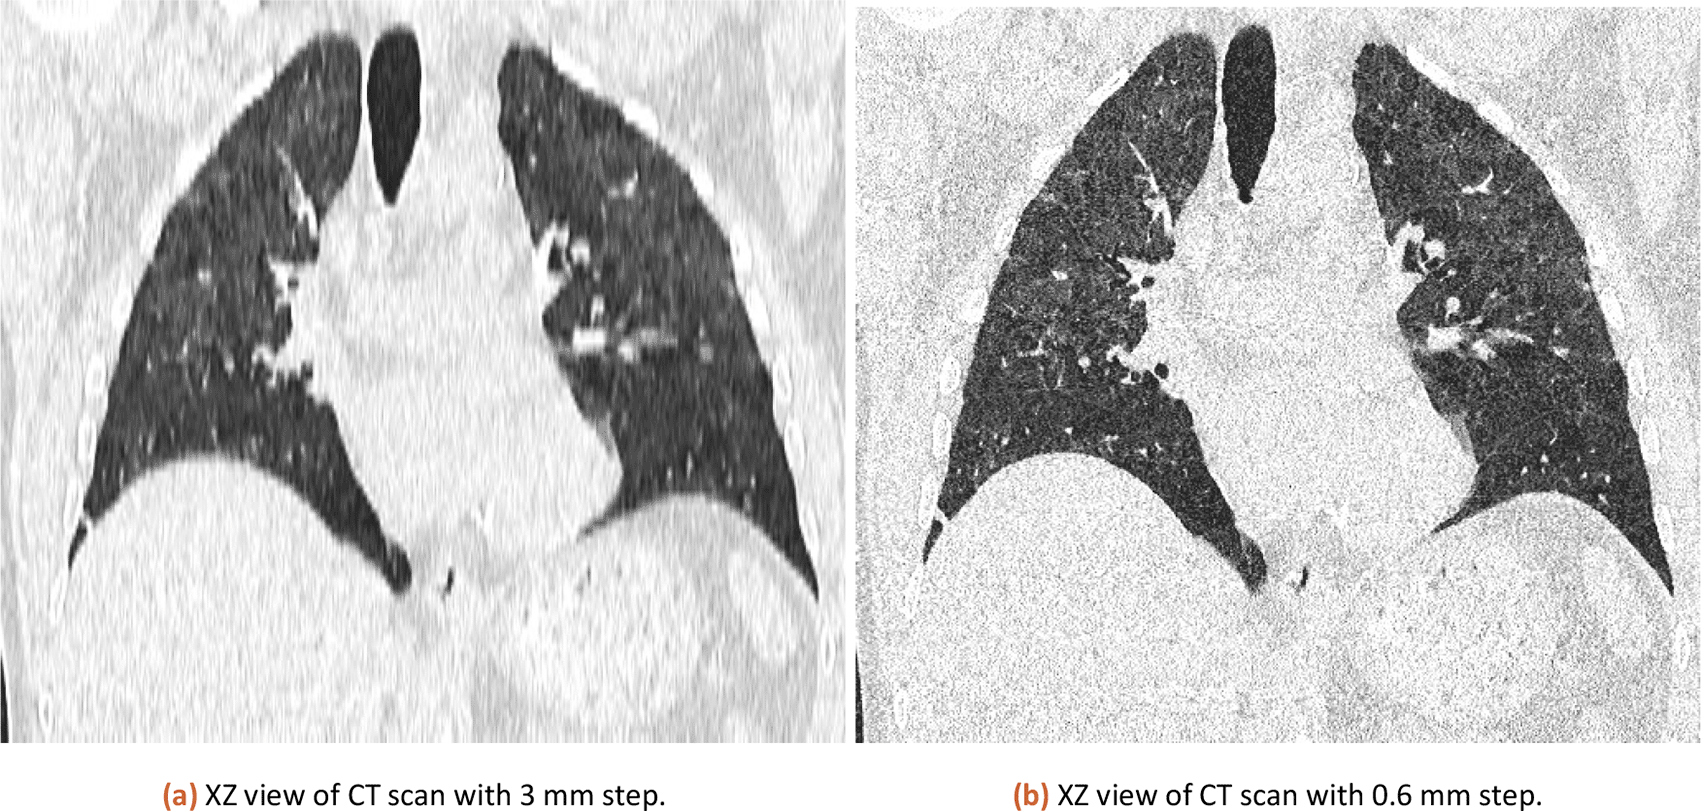

The tool has been tested both 3 mm slicing and 0.6 mm slicing CT images. The results were similar in percentage and the final CT score was the same.

The international standard for saving DICOM files defines 3 mm slicing of CT data as the default way. However resaving data as TIFF (losing voxel information) or using different slice thicknesses (like 0.6 mm slicing) may result in a different result. In theory, 0.6 slicing would provide 5 times more detailed sampling in the Z-axis. However, in practice it is different.

The same CT dataset exported with 0.6 and 3 mm slices (XZ view for comparison is in Figure 3) was analyzed with our tool with a lung threshold of 0-155 and a pneumonia threshold of 47-115. The results can be found in Table 1. The error from a comparison of 3 mm and 0.6 mm slicing is estimated at 0.58 %. The used CT is available in the attached published dataset as CT1_1 (0.6 mm slicing) and CT1_2 (3 mm slicing).